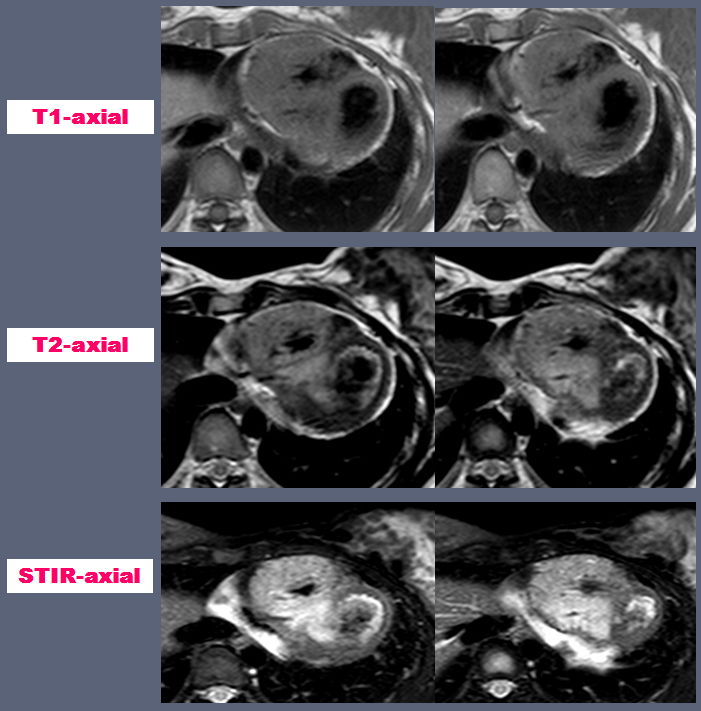

| 22yr / F, C.C. : Chest pain for 5 years, Anterior, mid-chest area, Aggravated by exercise, improved by resting, Dizziness (+), Palpitation (+) |